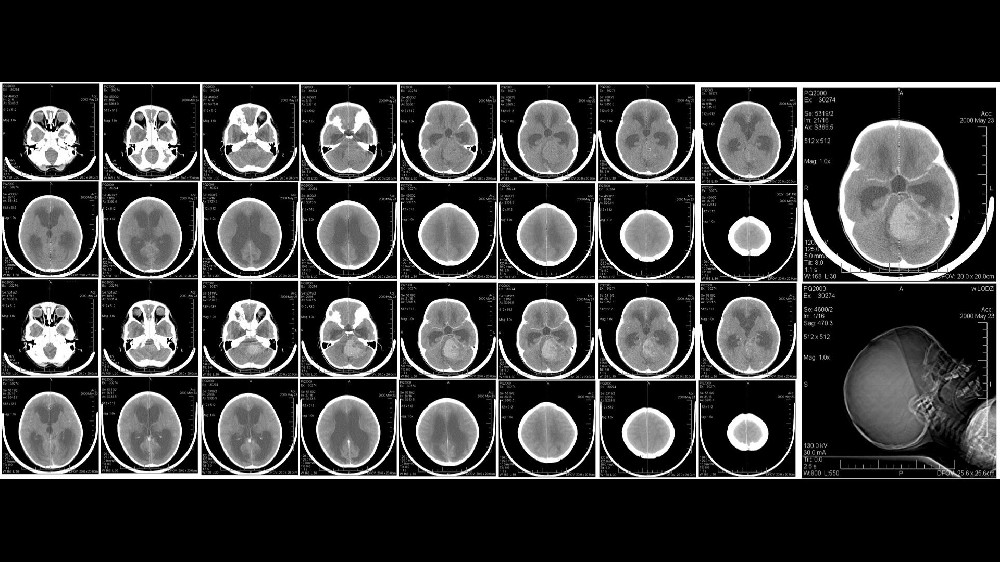

髓母細胞瘤的分期與存活率

瞭解疾病進展與本地資料洞察

髓母細胞瘤的病程分為四個不同的臨床階段,分別顯示腫瘤的位置、大小和轉移擴散情況。了解這些階段和相關的存活率,特別是與香港和亞洲人口相關的階段和存活率,有助於調整病人的期望,鼓勵及早介入治療。

第 1 期 - 早期髓母細胞瘤

第一期的髓母細胞瘤通常較小、定位精確,且擴散程度極低。在此早期階段發現的腫瘤可提供更多的治療機會,預後也非常良好。

通常僅限於直徑小於 3 公分的單一可切除腫塊。

標準治療包括手術切除,通常會結合局部放射治療。

包括香港和亞洲醫院的數據在內的經驗證據顯示,85% 在治療後 5 年的存活率令人鼓舞。

第 2 期 - 中期髓母細胞瘤

在第 2 期,髓母細胞瘤在空間上仍相對有限,但可能有輕微的組織侵犯或體積增大,對於完全切除手術提出了更高的挑戰。

腫瘤超過 3 公分,或腫瘤侵犯附近的小腦結構。

治療方案通常包括綜合手術、專門針對殘留癌細胞而設計的大範圍放射治療,偶爾還會進行化療。

亞洲患者群組的五年存活率仍然很高,根據香港腫瘤中心的臨床試驗統計,存活率介於 70%-85% 之間 (2024)。

第 3 期 - 晚期髓母細胞瘤

第 3 期髓母細胞瘤的特徵是腫瘤的侵襲性和局部擴散性增加,尤其是沿著腦脊液路徑擴散,對治療造成相當大的挑戰。

區域性擴散至整個腦脊液路徑,通常會達到腦部或脊髓的其他部分。

密集的多模式治療通常會結合手術、覆蓋較大中樞神經系統區域的放射線治療,以及定期的侵略性化療週期。

亞洲腫瘤學界的實際治療資料,特別是香港醫療機構的出版物顯示,由於治療複雜,5 年存活率在 50-70% 之間。

第 4 期 - 轉移性或高風險髓母細胞瘤

第 4 期是由中樞神經系統內或以外的遠端轉移所決定,代表一種侵略性、具挑戰性的臨床情況。

廣泛的轉移發病可達到遙遠的中樞神經系統地區,有時甚至是顱外,使得治療策略變得非常複雜。

複雜的系統療法整合了廣泛的化療、基於新陳代謝腫瘤學原理的尖端標靶治療(包括葡萄糖新陳代謝抑制或谷氨酰胺新陳代謝靶向),以及全面的放射策略。

亞太地區臨床研究報告的存活率顯示,髓母細胞瘤在診斷後三年的存活率只有 20-35%,但研究進展顯示,透過新穎的治療策略,例如由劉國龍教授等專家開創的代謝療法,以及 2024 年發表在《自然醫學》上的研究,髓母細胞瘤有可能變成一種可控制的慢性疾病。